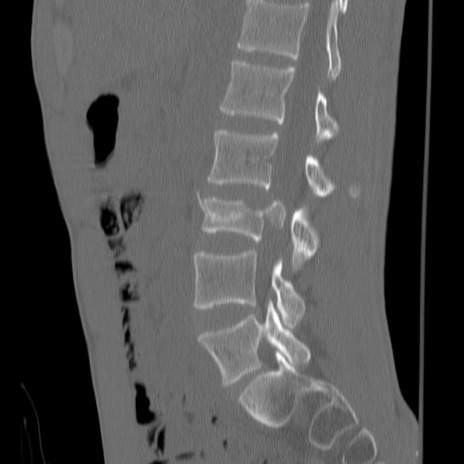

症例3 腰椎CT(矢状断像)

腰椎CT